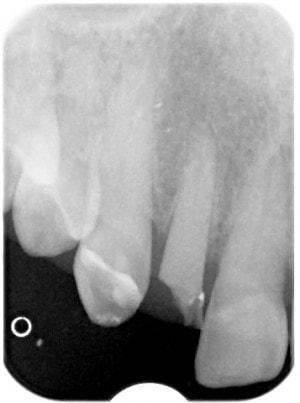

PA #7

-

Tooth #7 is vital

Crown would require root canal and post for retention. Unfortunately, there is no ferrule for a crown.